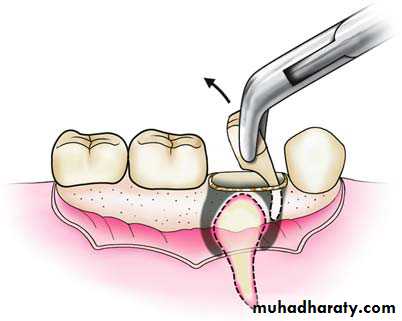

This technique is used for the roots of posterior mandibular teeth, where the buccal bone is dense and hard. After reflecting an envelope flap in these cases, a groove is created using a round bur between the buccal bone and the root, which makes enough room to allow for the positioning of the elevator.The blade of the T-shaped elevator is then seated in the groove, which luxates the root upwards, using the external oblique ridge as a fulcrum